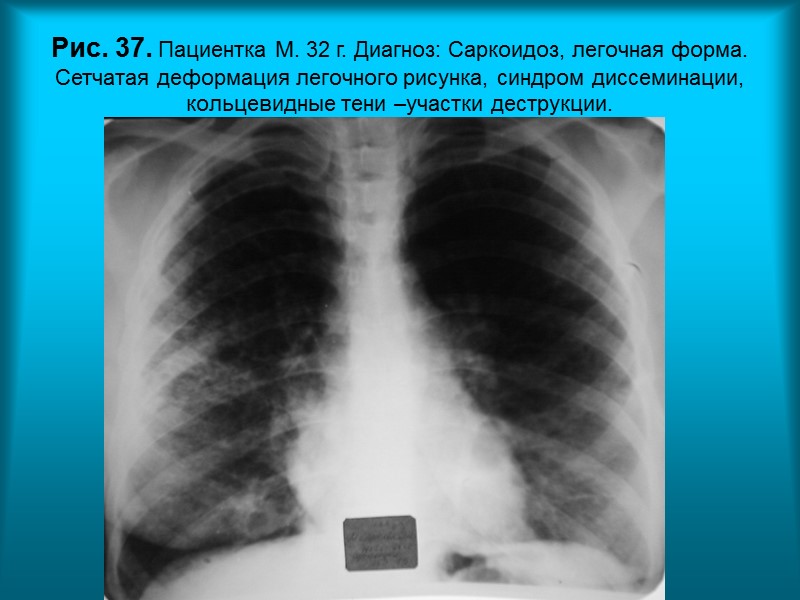

Н.С. Воротынцева. С.С. Гольев Рентгенопульмонология Рис. 37. Пациентка М. 32 г. Диагноз: Саркоидоз, легочная форма. Сетчатая деформация легочного рисунка, синдром диссеминации, кольцевидные тени –участки деструкции.